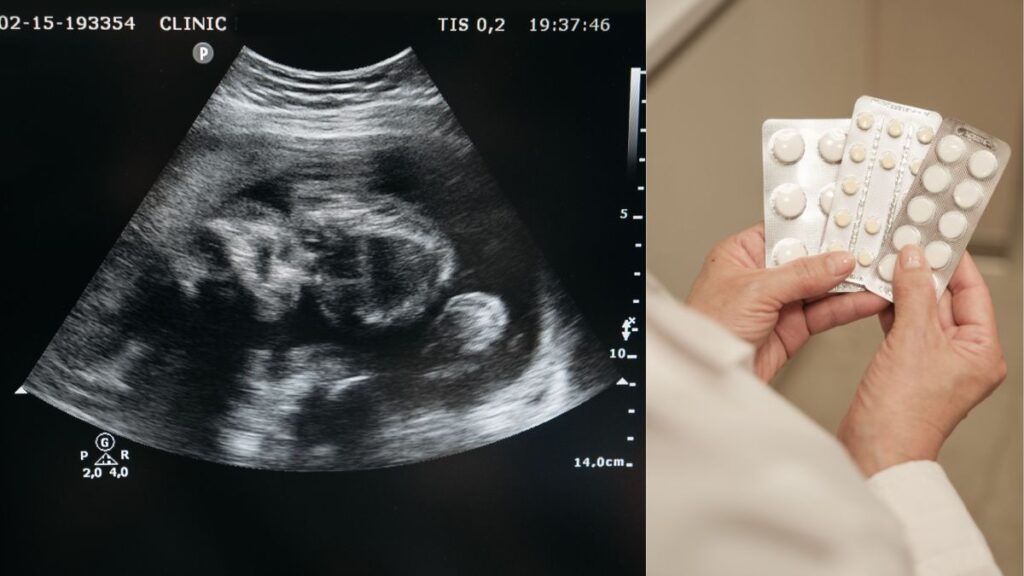

A 31-year-old woman in the state of Georgia, Alexia Moore, has been charged with attempted murder after taking abortion pills to end her pregnancy. The case has drawn strong reactions in the face of the state’s strict abortion laws.

Doctors at the hospital delivered a premature baby girl, who had a weak heartbeat and struggled to breathe. She survived for only about an hour, thus drawing attention from a hospital security officer, who then reported Moore to the police.

On further investigation by the police, it was found that Moore had been around 22 to 24 weeks pregnant at the time of her admission. Investigators also concluded that the woman confessed to taking drugs to induce a miscarriage.

However, on March 4, Moore was charged with attempted murder. She was also charged with the possession of a controlled substance and dangerous drugs like oxycodone and misoprostol.